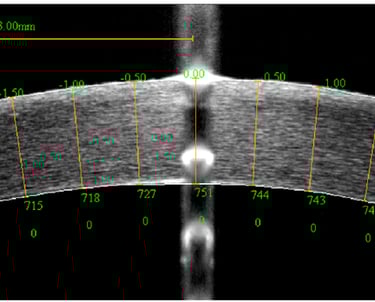

A paquimetria é um exame que mede a espessura da córnea, uma informação crucial para o diagnóstico de condições como o ceratocone e para a avaliação pré-operatória em cirurgias refrativas. O exame é rápido e indolor, realizado com um aparelho que emite uma onda ultrassônica ou luz para medir a espessura corneana com precisão. Esses dados são fundamentais para garantir a segurança e o sucesso de intervenções cirúrgicas nos olhos.